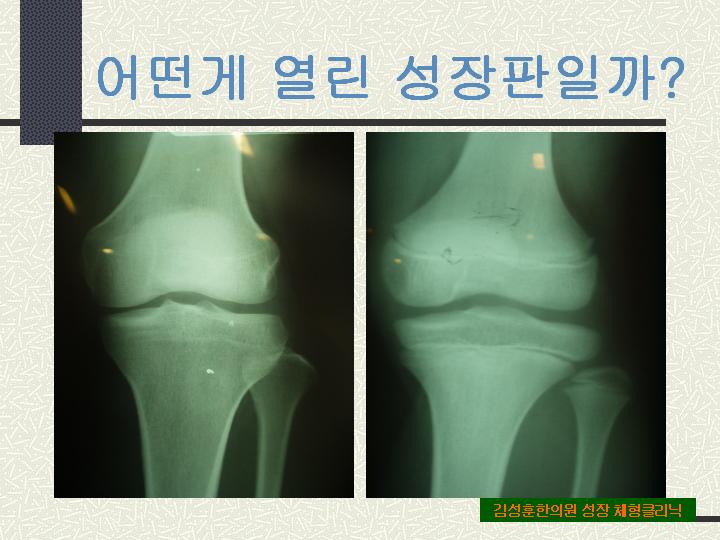

32.¾î¶²°Ô ¿­¸° ¼ºÀåÆÇÀϱî?

¹«¸­ÀÇ ¼ºÀåÆÇ¿¡ ´ëÇØ ´ÝÇô ÀÖ´Â »óÅÂ¿Í ¿­·ÁÀÖ´Â »óŸ¦ º¸¿©ÁÖ´Â »çÁøÀÔ´Ï´Ù. ¿À¸¥ÂÊÀÌ ¿­¸° ¼ºÀåÆÇÀÇ »çÁøÀÌ°í ´çÀåÀÌ¶óµµ Å°°¡ ¾¦¾¦ Ä¿¹ö¸± °Í¸¸ °°Àº ¸ð½ÀÀÔ´Ï´Ù.